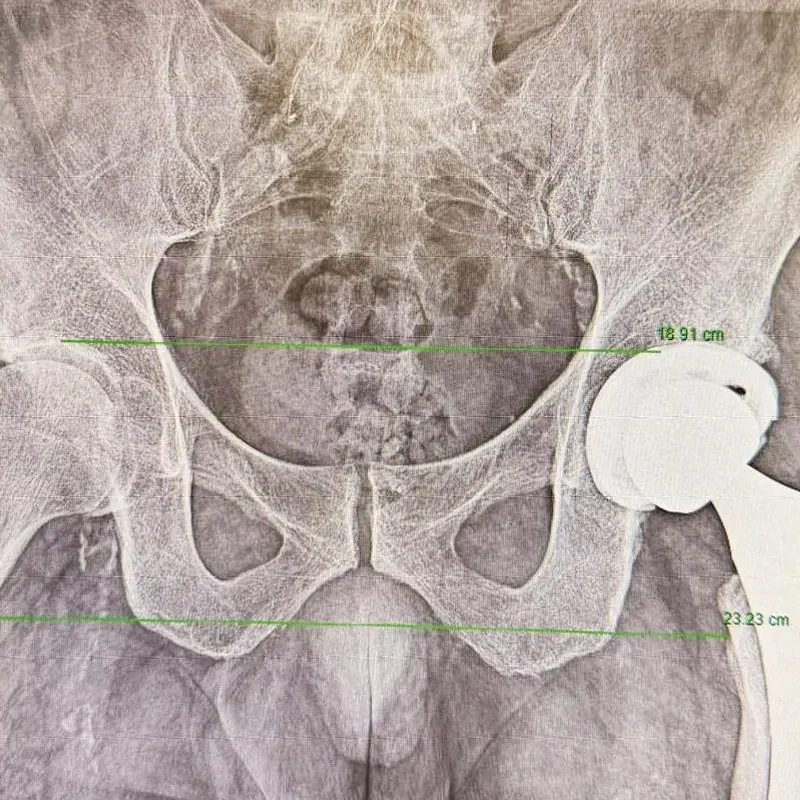

Cirugía Ortopédica